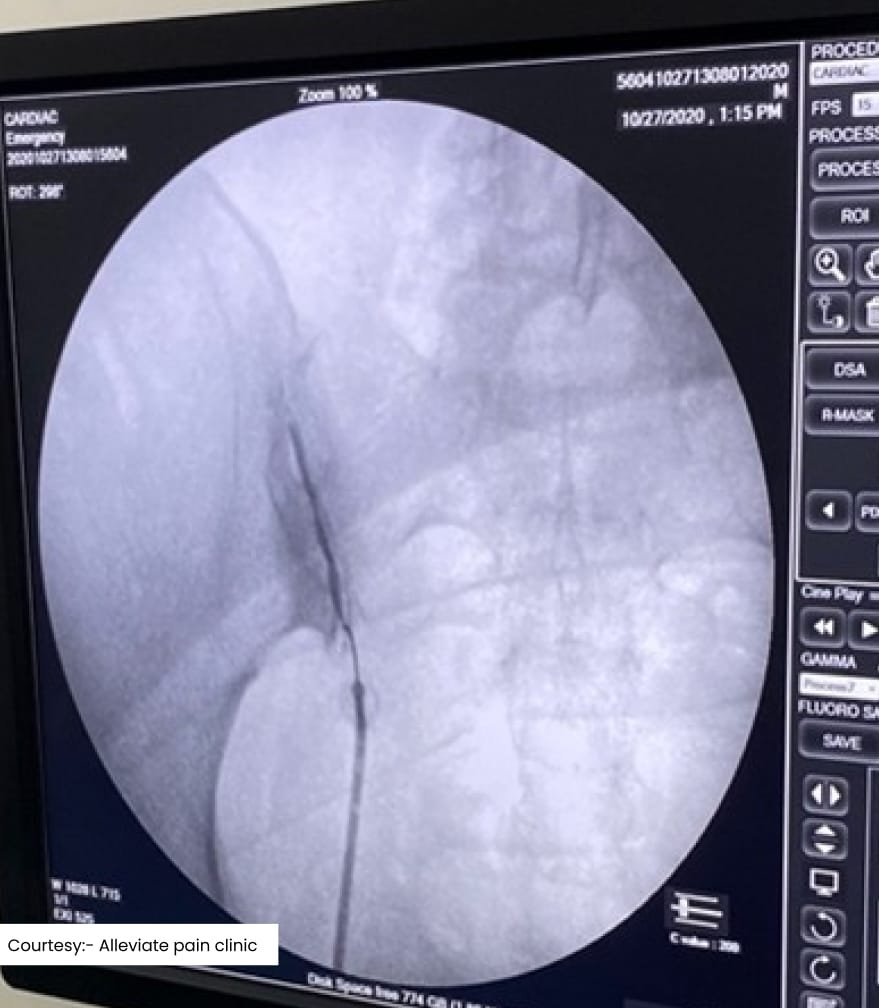

Scan 3

Cervical Epidural Injection done under fluoroscopy

Epidural steroid injections are commonly used to reduce inflammation around the spinal nerves. These injections can alleviate pain caused by herniated discs, spinal stenosis, or radiculopathy. By delivering corticosteroids directly into the epidural space, usually in the cervical or lumbar region depending on the site of the pathology, this procedure can provide quick relief from acute and chronic low back pain.